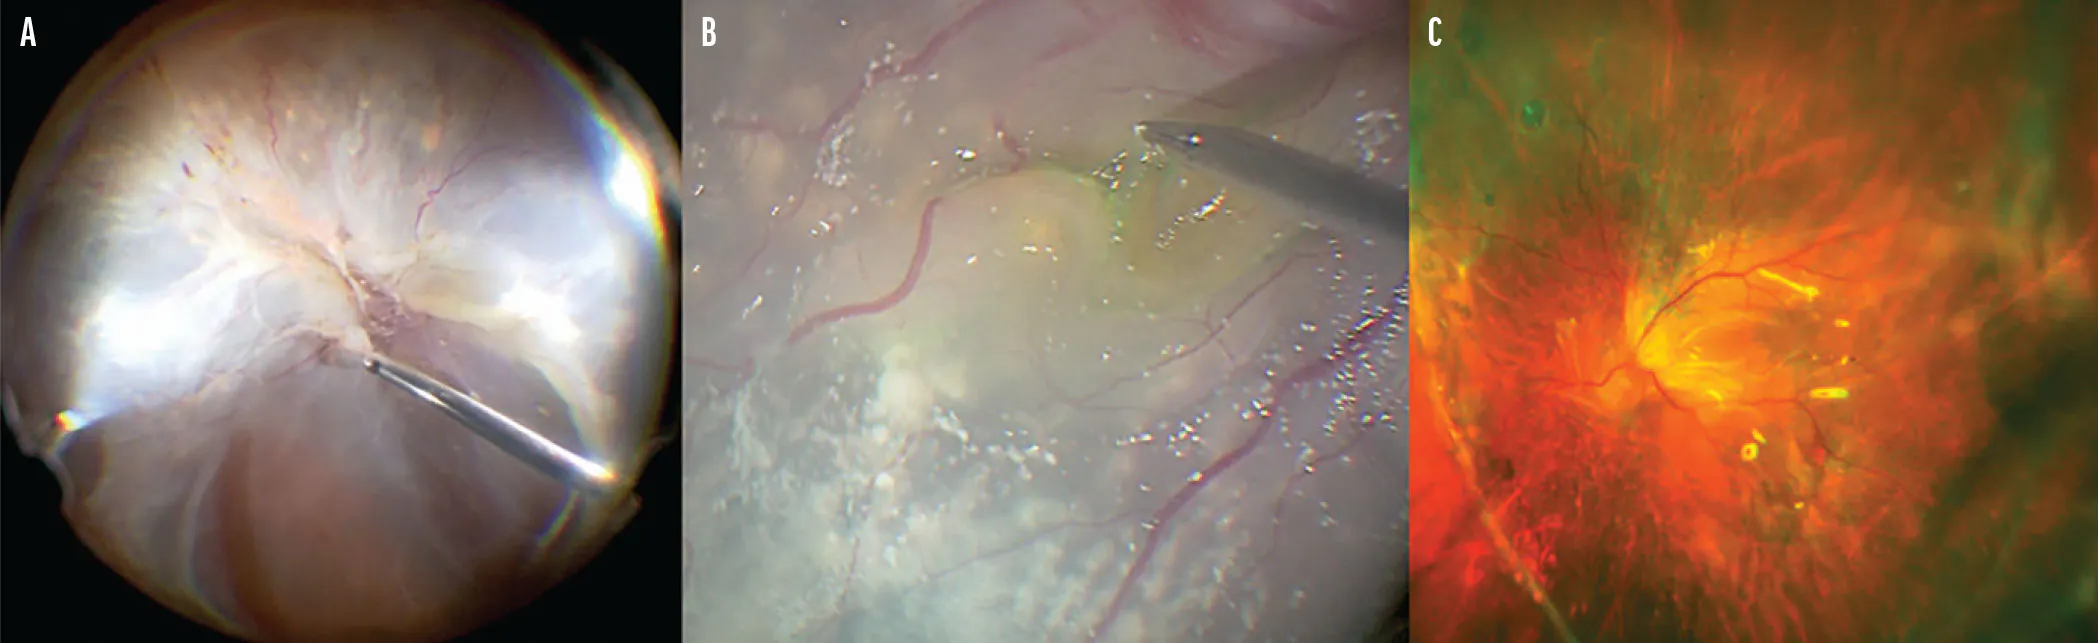

Figure 1. Intraoperative fundus imaging showed a total rhegmatogenous RD with grade C PVR (A). After inferior retinectomy and extended ILM peeling under PFO (B), the retina was successfully reattached postoperatively (C).

A 52-year-old man presented with a 3-year history of progressive vision loss and a recent mature cataract in his left eye. His VA was hand motion OS, and his IOP was 5 mm Hg OS. B-scan ultrasonography revealed a total RD in the left eye, and the patient underwent phacovitrectomy. After cataract extraction, intraoperative findings confirmed a chronic total RD and grade C PVR (Figure 1A).

During vitrectomy, dense preretinal membranes were removed from the posterior pole to the periphery. Subretinal bands were removed bimanually through an inferior retinectomy. The retina was flattened under PFO, followed by extended ILM peeling from within the vascular arcade and beyond the arcade toward the retinectomy site to relieve residual traction (Figure 1B). Endolaser photocoagulation was applied to the inferior retinectomy margin, followed by silicone oil tamponade.

After surgery, the patient’s retina remained reattached; his VA improved to 20/400 OS and IOP was 20 mm Hg OS (Figure 1C).